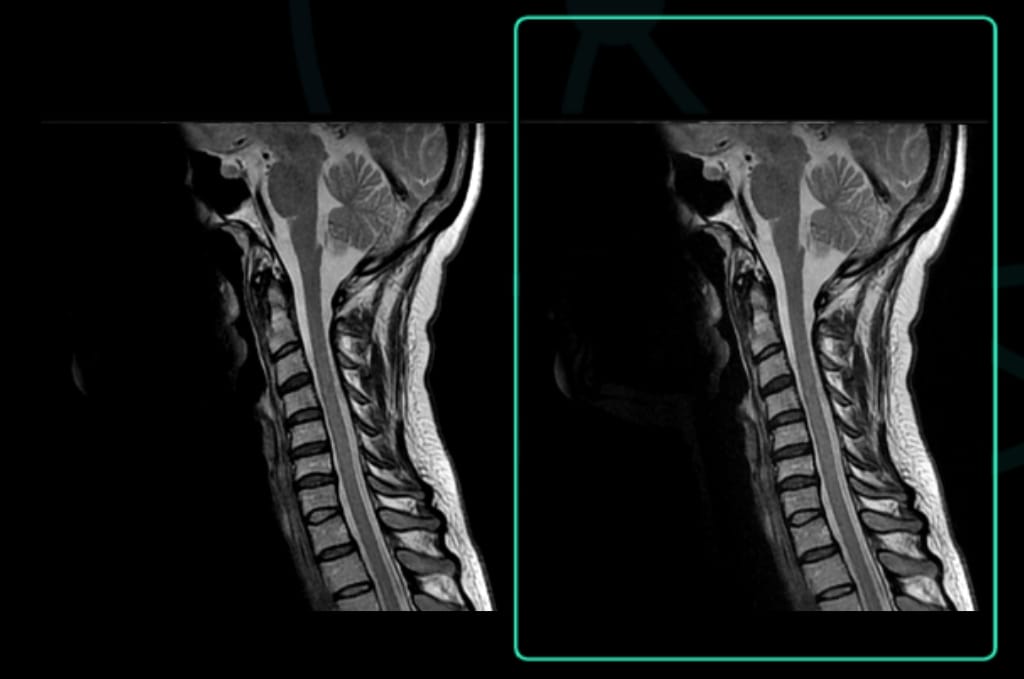

Varredura original: 2:10

Tempo Acq: 320×320

Varredura acelerada aprimorada por SubtleMR™

Tempo Acq: 1:09